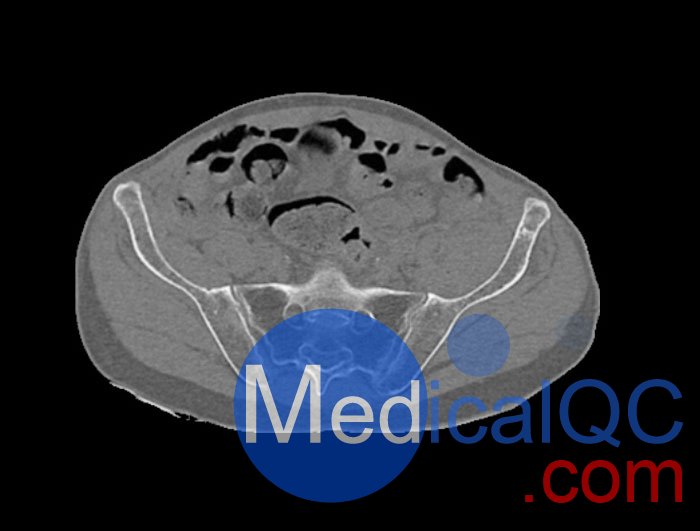

WEK54-01股骨頸骨折骨盆模型,WEK54-01骨盆模體模擬沒有靜脈造影劑的骨盆(天然)。它覆蓋了整個骨盆,直到第五腰椎。

左側(cè)股骨頸移位骨折。

該模型可用于 CT(包括 CBCT)和射線照相,以評估和優(yōu)化成像性能和后處理應(yīng)用,包括支持 AI 的應(yīng)用。它也適用于培訓(xùn)目的。

WEK54-01股骨頸骨折骨盆模型,WEK54-01骨盆模體提供了對軟組織和骨組織的詳細(xì)而逼真的模擬??障吨刑畛渲s-160HU的纖維素-聚合物復(fù)合材料。

骨骼和軟組織的逼真模擬。